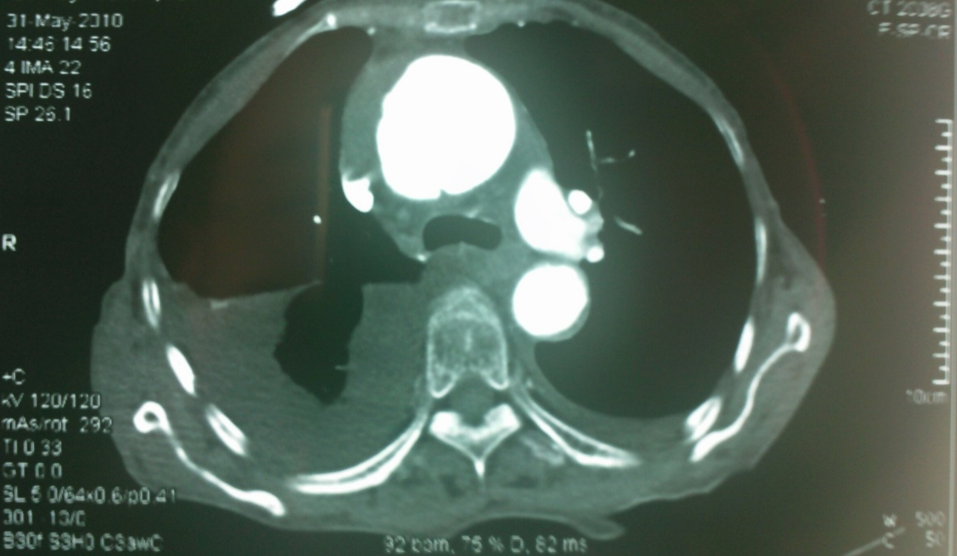

我们早期曾遇到一例升主动脉夹层治疗失败的病例(因失败未留存完整影像),但事后复盘发现,根本原因在于对主动脉三维解剖认知不足。当时采用预开窗技术,支架释放后发生近端移位和远端扭转,导致左颈总动脉与头臂干被遮蔽,最终需紧急补救性支架+两次搭桥手术。

全麻下双上肢穿刺,右股动脉切开,左上肢路径造影,右上肢进保护性导丝,对支架预开窗后植入升主,因破口较大,支架近端掉入破口,远端扭转遮蔽左颈总动脉及头臂干,窗口对破口,再次植入一枚38-80支架,封住近端破口后,以8*60支架开放右侧头臂干,6*10人工血管行右锁骨下-左颈总搭桥,取颈前静脉行左椎动脉-人工血管搭桥,之后造影,头臂动脉均通常,术后约2小时患者清醒。